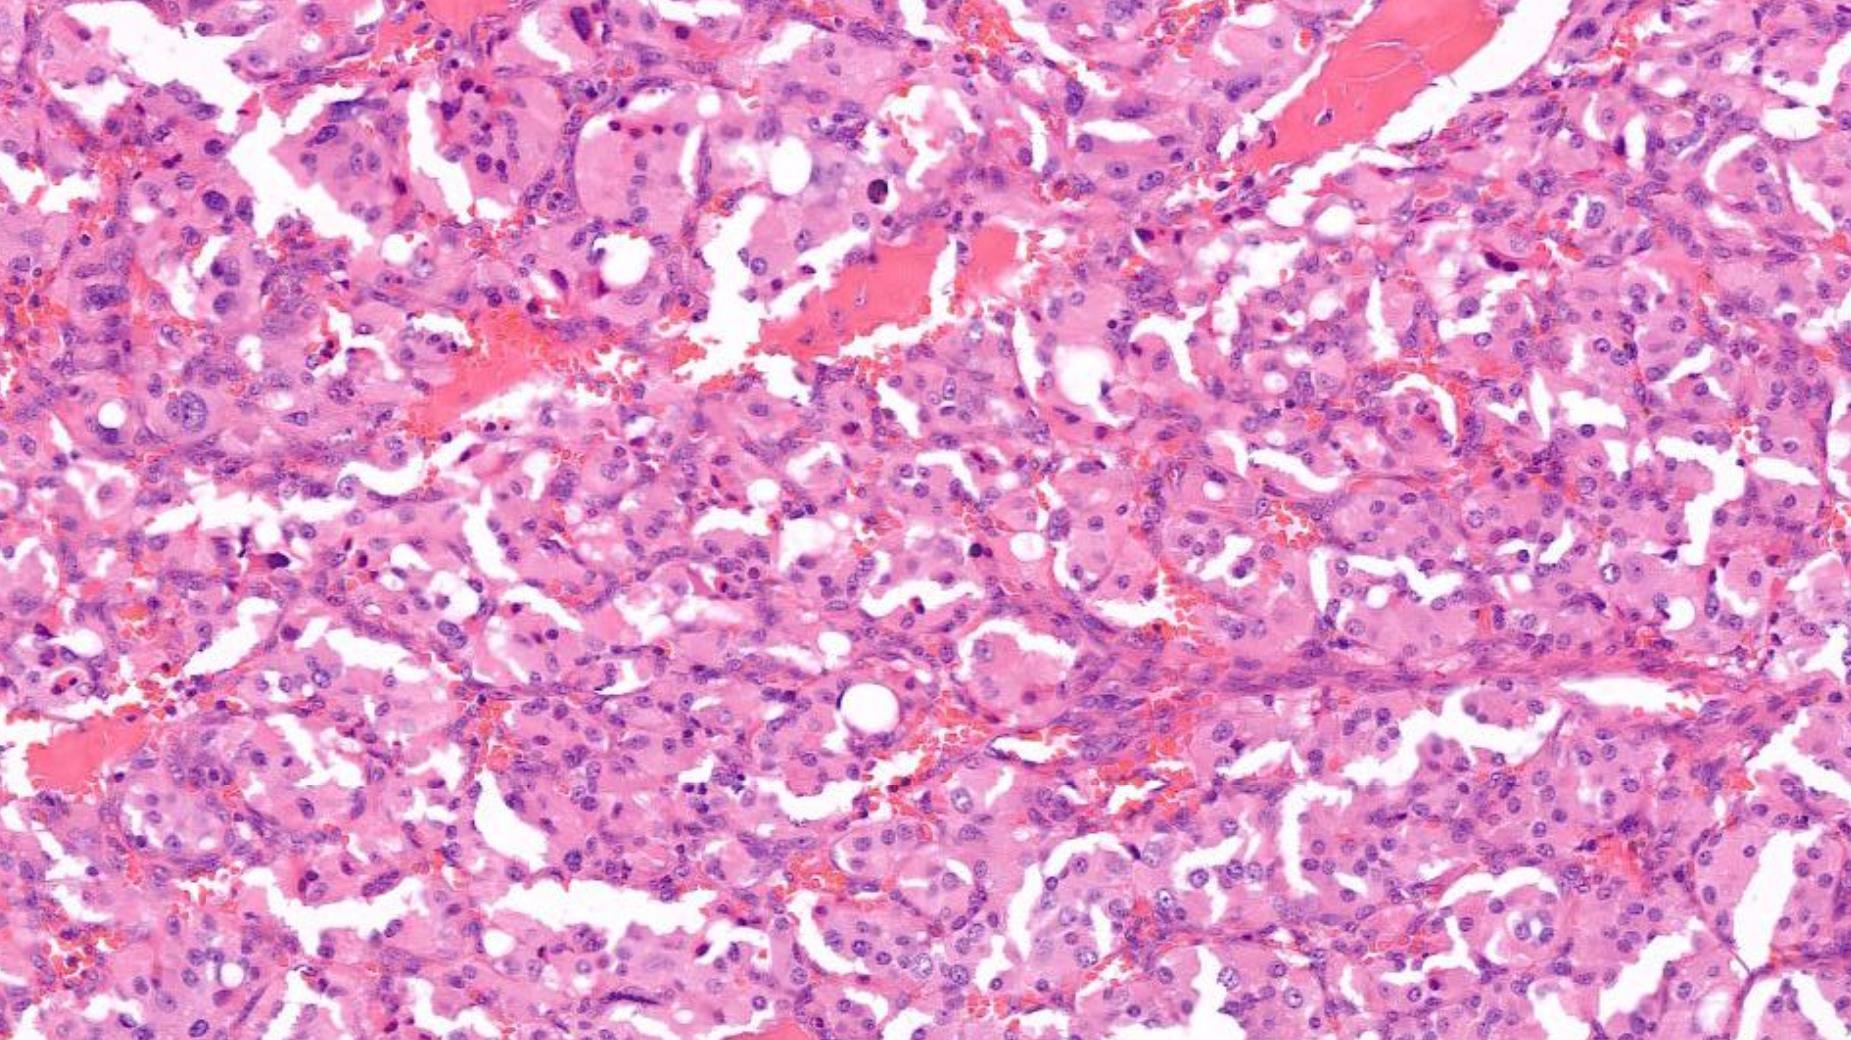

Case 12 55-year-old, Male Lump In Parotid.

Case 12 Diagnosis

Acinic cell carcinoma

Notes • Lymphoid

• ACC • MEC • Prognostic factor- better

indicator • ACC can undergo HG transformation

stroma